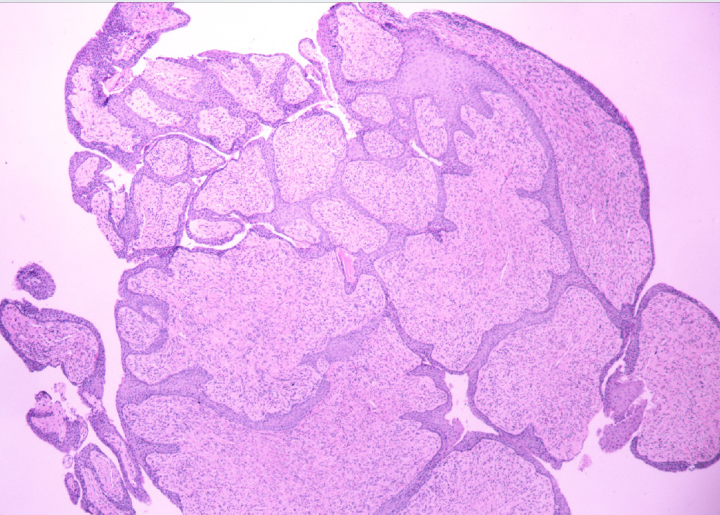

Devido à suspeita de onicomatricoma, a paciente foi encaminhada para cirurgia. Foram realizadas duas incisões na dobra ungueal proximal, a qual foi rebatida, expondo o tumor. A exérese da unha permitiu a visualização de projeções digitiformes na área da matriz (Figuras 5 e 6). Realizamos exérese completa do tumor e fechamento primário das incisões na dobra ungueal proximal (Figura 7). A histologia demonstrou hiperplasia digitiforme revestida por epitélio escamoso formando projeções, confirmando o diagnóstico de onicomatricoma (Figura 8).

Exames de imagem, como radiografia, ultrassonografia e ressonância nuclear magnética (RNM), podem auxiliar no diagnóstico da lesão, porém na maioria dos casos os exames clínico e dermatoscópico associados ao exame anatomopatológico são suficientes para o diagnóstico, assim como no caso relatado.8,9 O exame anatomopatológico demonstra um tumor fibroepitelial composto por duas porções. A primeira, proximal, localiza-se sob a dobra ungueal posterior, caracterizada por invaginações epiteliais preenchidas por espessa zona queratinizada em forma de “V”, estroma fibrilar e fibrocítico bem delimitados, além do espessamento da placa ungueal. A zona distal, na lúnula, caracteriza-se pelas projeções digitiformes, perfurações na placa ungueal e penetração profunda e mal delimitada do estroma conectivo na derme.10